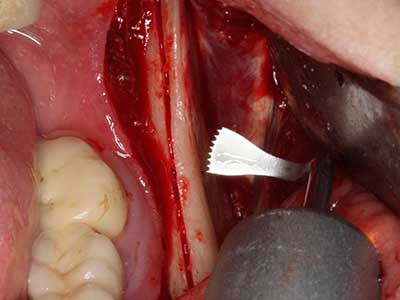

Sollen chirurgische Eingriffe mit unmittelbarer Knochenbeziehung an empfindlichen Strukturen wie Blutgefäßen oder Nerven erfolgen, so bergen rotierende Instrumente ein erhebliches Potential an iatrogener Schädigung. Gerade bei Nervdarstellungen nach iatrogener Schädigung, oder aber im Zuge einer Nervlateralisation für resektive und rekonstruktive Eingriffe oder Implantatinsertionen können piezoelektronische Geräte hilfreich sein Knochendeckel zu präparieren und nervnahe Hartgewebsanteile zu entfernen (Abb. 17-20). Ein leichter Kontakt des Nervstrangs zur Piezospitze bleibt dabei in der Regel folgenlos – allerdings kann eine unvorsichtige Vorgehensweise mit sägeartigen Bewegungen bzw. Ansätzen bei noch vorhandener knöcherner Unterlage durchaus temporäre oder aber auch permanente Nervschädigungen verursachen. Das Risiko einer solchen Schädigung wird jedoch als wesentliche geringer eingeschätzt als unter Anwendung von Säge- oder Fräsinstrumenten (Pereira, Gealh et al. 2014).

Abb. 18: Präparation eines Kortikalis-Deckels mit der Piezo-Knochensäge (Piezomed, W&H).

Abb. 20: Der entnommene Knochendeckel wird readaptiert und durch eine Osteosyntheseschraube (KLS Martin, Tuttlingen) fixiert.